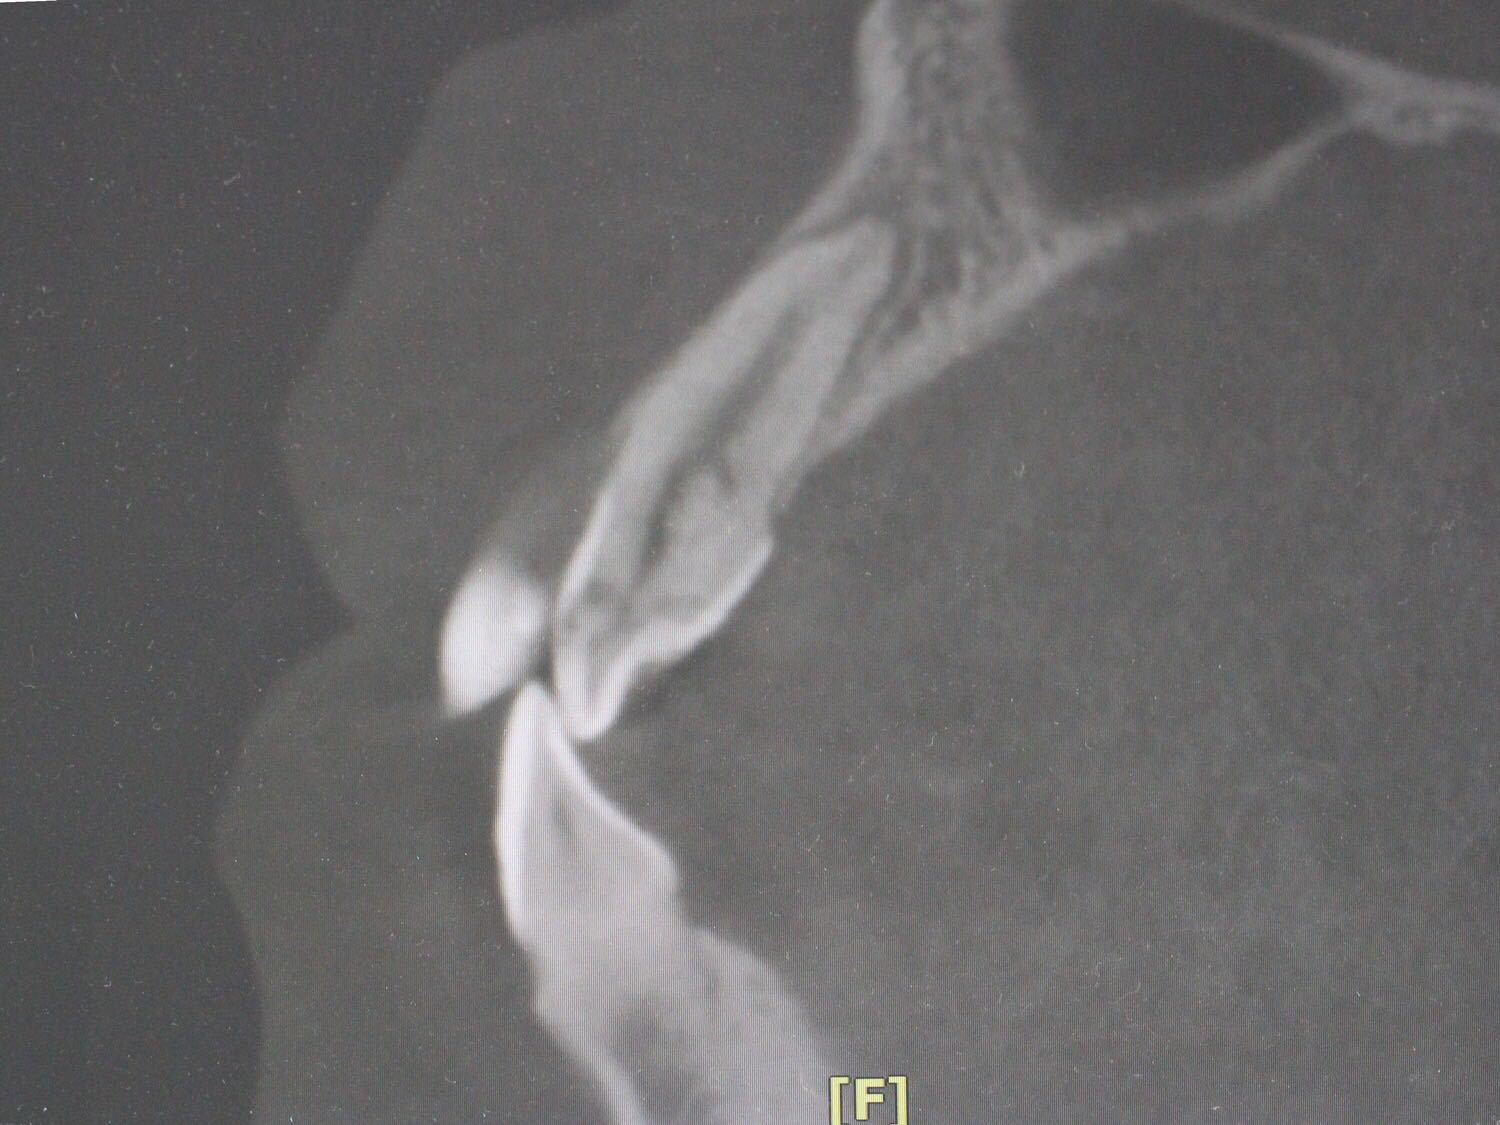

检查:12牙未见明显龋坏,探(-),冷(-),叩(++),无明显松动,牙髓电活力测试无反应,唇侧牙槽粘膜处未见窦道。 X线片:12牙根尖周暗影?

诊断:12牙牙髓坏死? 治疗方案: 1、12牙根管治疗+充填治疗+冠修复 2、12牙择期治疗 3、12牙显微根尖外科手术 4、12牙拔除 5、12牙观察 治疗计划:与患者交流沟通并详细介绍每种治疗方案、费用、时间、预后等,由于患牙根尖病变范围较大,预后欠佳。患者知情、同意并选择方案2,签署知情同意书。 12牙涡轮机开髓,探查根管口,10#,15#K锉疏通根管,根长测量仪测量根管长度,12牙22.5mm,髓腔和根管内放置根管润滑剂,S3扩锉至2506,拍片试尖,X线片示主尖合适。次氯酸啊冲洗根管,P5荡洗,纸尖干燥根管,置氢氧化钙,Caviton暂封。

处置:12牙去暂封,去棉球,根管及髓腔消毒并再次测量并确定根管长度,干燥后,显微镜下使用根尖孔生物材料加大锥度牙胶尖及热牙胶行根尖屏障封闭成形及根管充填,再拍X线片检查根充效果,X线片示根充良好,窝洞消毒,暂封。 医嘱:不适随诊,勿用患牙进食